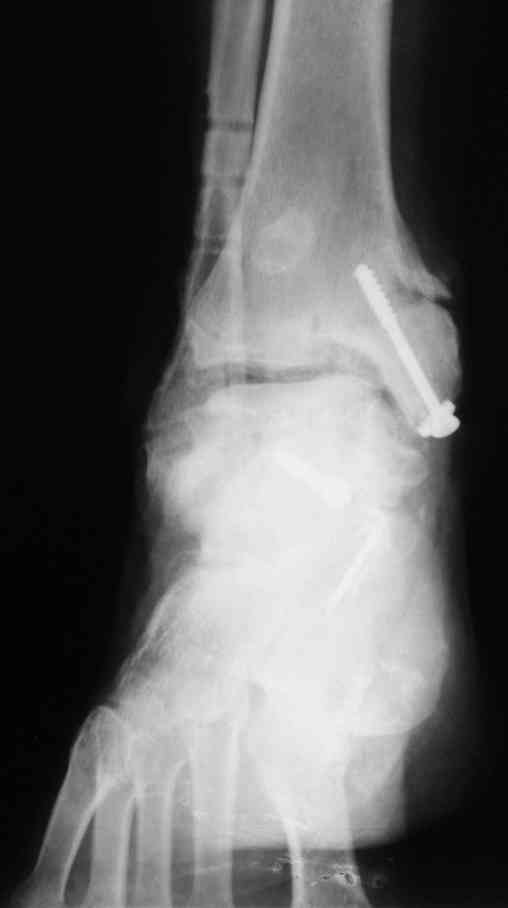

И второй случай из недавней ташкентской практики, (извините за качество ренгенограммы и только в одной проекции) случай падения с высоты (кстати моего друга - известного киноактера) - открытый

смещенный перелом тарана, с переломом переднего края дистального эпиметафиза большеберцовой кости.

При поступлении в приемной сделана первичная обработка с ушиванием открытой латеральной раны и вытяжением за пятку.

Из-за отсутствия времени пришлось оперировать на второе утро, из материала, что имеем на месте, фиксирован двумя шурупами, а третий-это контур сломанного жойстика в 4 мм. На дистальный медиальный конец тибиа antiglide 3.5 мм пластина. Через пару дней выписан и несмотря на предупреждение, самостоятельно начал нагрузку в 4 недели, время не ждет, снимается в боевике в Росийской Федерации.